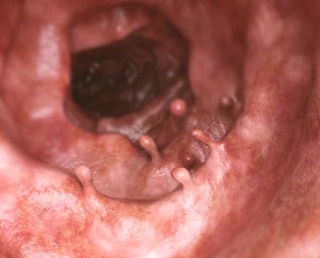

선종과 용종은 대장내시경을 통해 주로 진단됩니다. 진단 이후에는 크기와 성질에 따라 적절한 치료가 진행됩니다.

- 대장내시경: 용종 및 선종을 직접 관찰하고, 필요시 즉시 제거할 수 있는 가장 효과적인 진단 및 치료 방법입니다.

- 조직 검사: 제거된 조직은 조직 검사를 통해 암으로의 진행 가능성을 평가합니다.

- 절제 방법:

- 작은 용종은 내시경으로 제거 가능합니다.

- 큰 용종이나 선종은 수술이 필요할 수 있습니다.